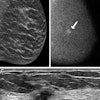

A 59-year-old woman with scattered density breasts. The lesion is only seen on the tomosynthesis slices. The case was not triaged at the 0 false-negative rate, however, as researchers increased the false-negative rate to 0.12 per 1,000 women screened; the AI software would have characterized this as a small invasive ductal carcinoma. Image courtesy of Dr. Emily Conant.When it came to triaging cases, the algorithm selected 33.4% of exams that would be suitable for triage because they were unlikely to have cancer. When age and breast density were added to the case score, that number rose to 58.6%.